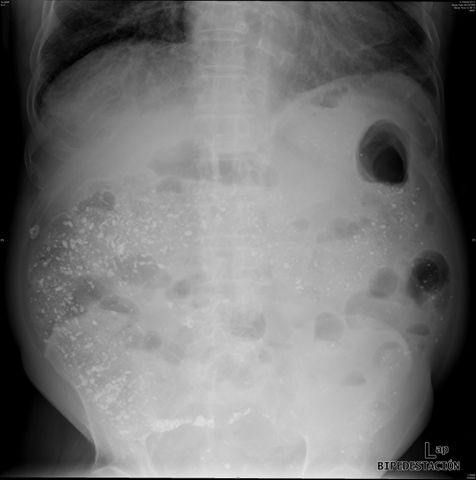

Suboclusión intestinal.